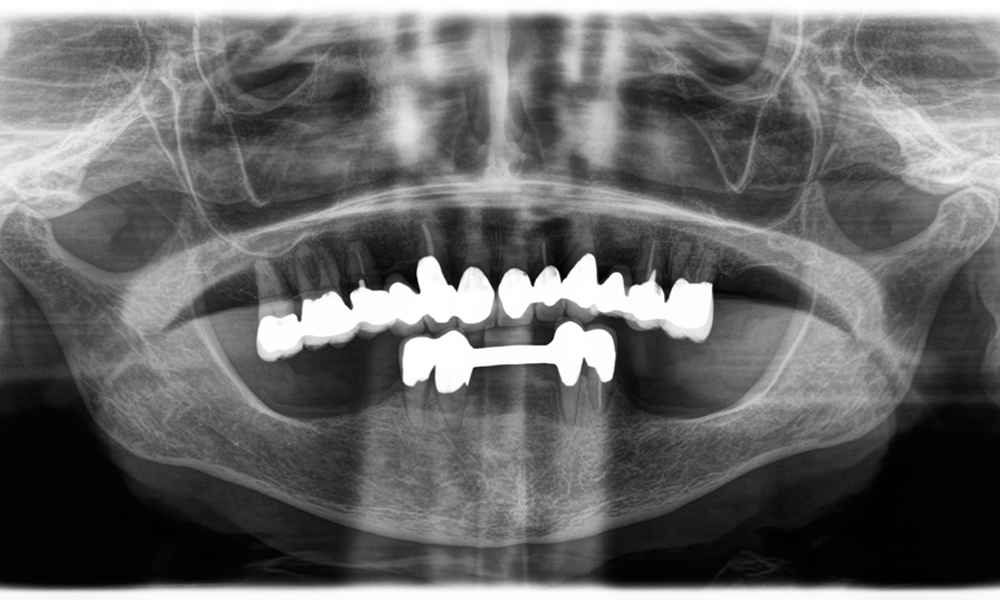

Provocarea consta în îndepărtarea a douăsprezece coroane fixate cu aliaj metalic, fără a deteriora dinții de susținere. Piesa de mână a fost utilizată pentru secționarea foarte precisă a straturilor ceramice și divizarea structurii metalice cu ajutorul unei freze din carbură, permițând astfel îndepărtarea coroanei cu un grad minim de traumatizare. În doar 30 de minute, vechile restaurări au fost îndepărtate, permițând pregătirea noii proteze, cu contur complet din zirconiu în regiunea posterioară și coroane fațetate anterior. Rezultatul a fost o restaurare completă, care a asigurat atât succesul funcțional, cât și cel estetic (vezi Fig. 1).